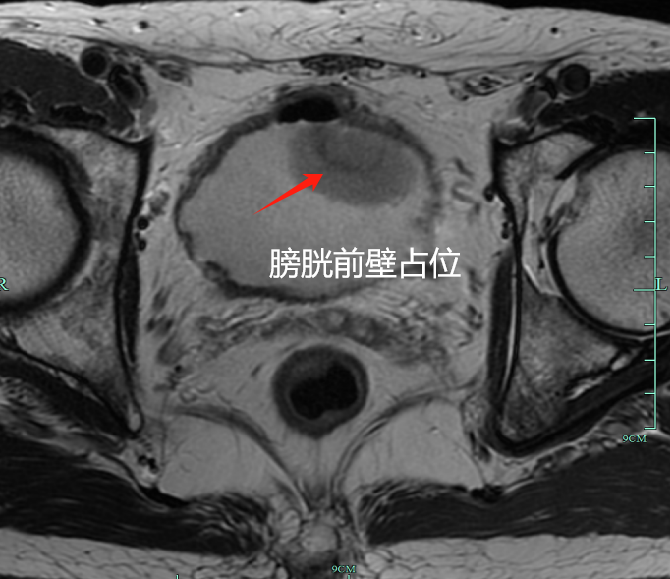

膀胱MR结果

最终的病理提示,亮哥得的是肌层浸润性高级别尿路上皮癌,癌细胞已侵犯膀胱肌层(T2期),更具侵袭性,也更容易转移。